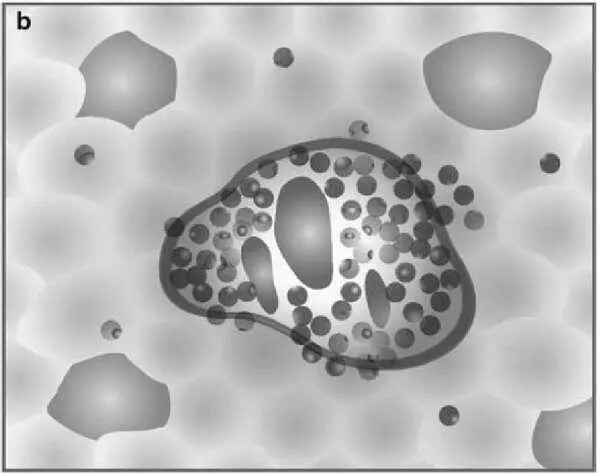

Разработчики ставили цель упростить шкалу. Оригинальность подхода заключается в том, что шкала представлена в виде 4 диаграмм, оценивающих некротические и воспалительные изменения в биоптате печени, и 4 диаграмм, оценивающих стадию фиброза .

Рисунок 5 – Схемы некротических и воспалительных изменений в печени (по Batts KP, Ludwig J.)

На рисунке представлена последовательная схема некротических и воспалительных изменений в печени при хроническом гепатите (по Batts–Ludwig). Воспалительная инфильтрация портальных трактов является обязательным компонентом поражения печени при гепатите и оценивается во всех системах. В оценочной шкале Баттс–Людвига выраженность гистологической активности гепатита градируется от 1 до 3 (a, b, c). На рисунке d представлена схема сливных некрозов в виде мостовидных некрозов, которые свидетельствуют о выраженной степени активности гепатита и соответствуют 4 стадии активности по системе Баттс–Людвига (Batts KP, Ludwig J. Chronic hepatitis. An update on terminology and reporting. Am J Surg Pathol 1995;19:1409–1417.15).